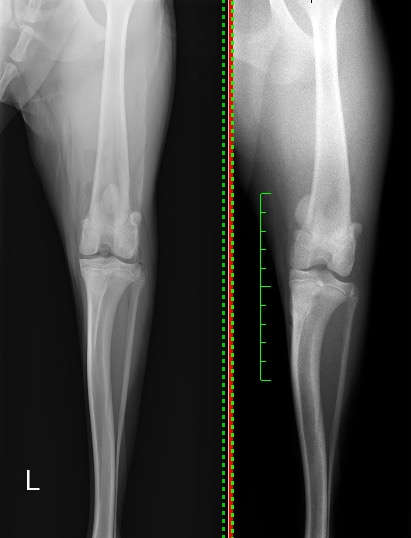

次の写真は右が術前の脱臼時、左が術後になります。

膝蓋骨が大腿骨の真ん中にしっかりと整復されているのが分かるかと思います。

今回の手術は通常のブロック型の滑車溝造溝術に近位側にウエッジ型の造溝術を加え、膝蓋骨が高い位置に来た場合でも脱臼しないようにしました。